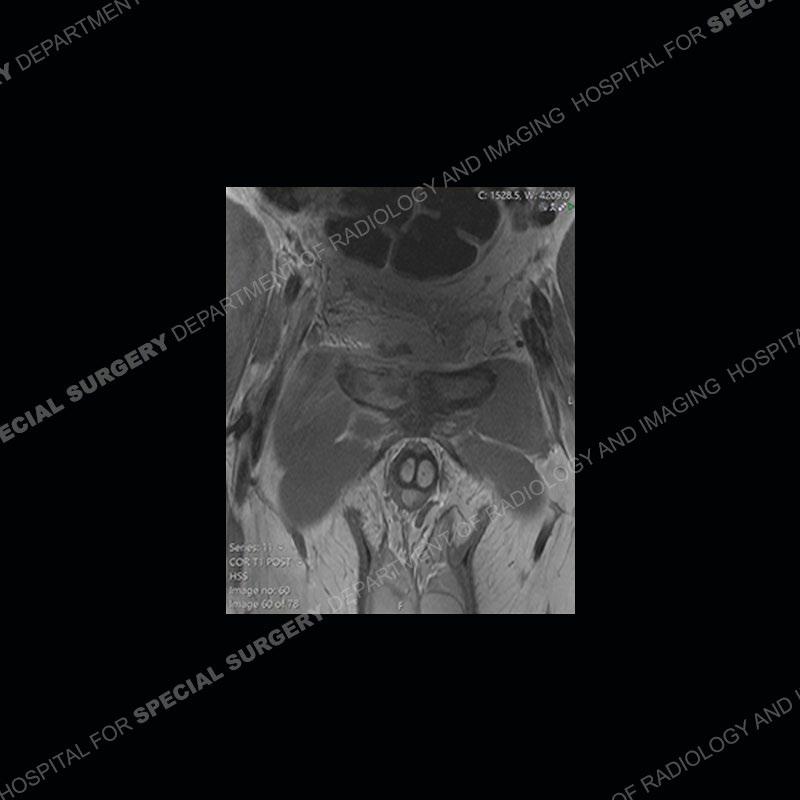

Subsequent MRI in a very short time interval shows markedly increased abnormality of the ramus and increased edema and “mass” of the soft tissue. Post contrast imaging shows multiple, rim enhancing collections of the soft tissue and similar albeit less conspicuous enhancing collection of the ramus.

Diagnosis: Osteomyelitis and Soft Tissue Abscess

The repeat MRI, with the marked degree of increased abnormality of the bone and soft tissue shifted the diagnosis to a high degree towards infection. Even the most aggressive of neoplasms would not have that the degree of change in a 3-day time span. The CT study was shown before the repeat MRI but actually occurred just after the repeat MRI. It helped confirm the destructive process of the ramus and particularly the abnormal architecture along the inferior margin. The patient went on to have a CT guided aspiration of one of the soft tissue collections with 4cc of purulent fluid obtained. A surgical irrigation and debridement of the bone and soft tissue was performed. A PICC line was placed and the patient is currently undergoing IV antibiotic treatment with a possible repeat irrigation and debridement.